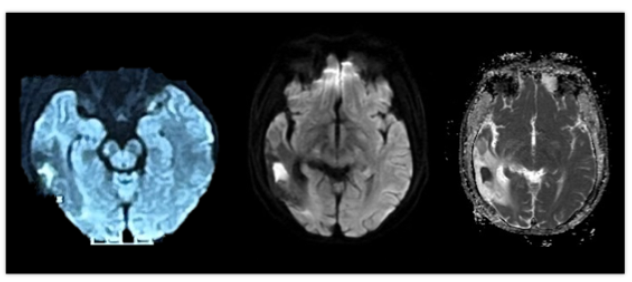

入院情况

1. 右侧颞叶持续弥散受限病灶

该病灶完全位于旧梗死灶内部,多次复查基本稳定(图2),未引起新的症状体征,考虑并非新发脑梗死灶。同时对比其他序列,该病灶也并非出血或T2穿透效应,考虑该“顽固的”弥散受限病灶可能与病灶内持续低灌注或局部坏死物质聚集有关。查阅文献,2023年德国研究者曾报道类似现象,在接受血管取栓治疗的急性脑梗死患者3~12个月随访过程中,37.2%患者可能存在原梗死灶内部持续弥散受限病灶,可能与原梗死体积较大相关。

图2 患者多次复查弥散受限病灶基本稳定